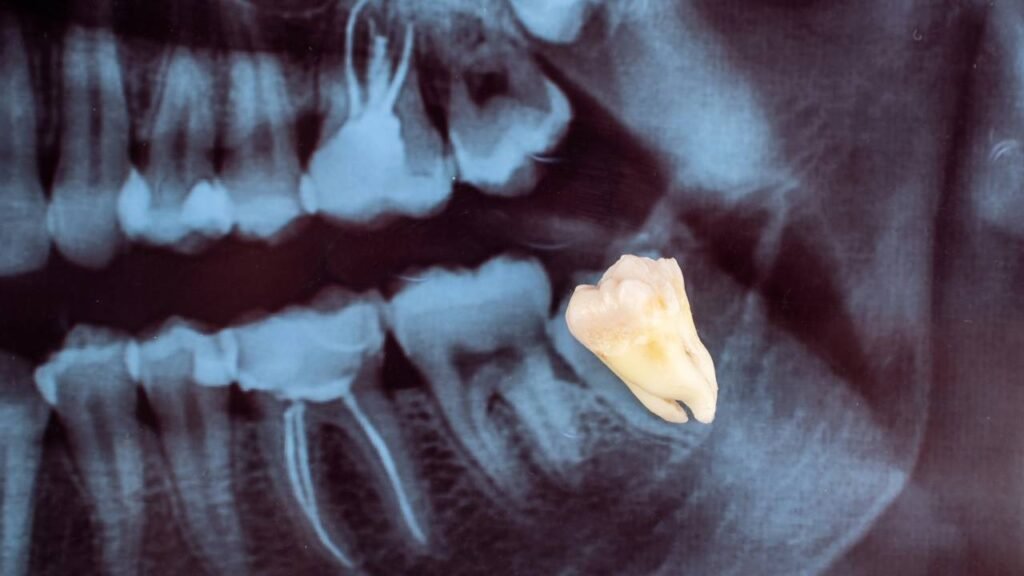

Outro motivo comum para remover o siso é a dificuldade de higienização, sobretudo quando o dente está parcialmente coberto pela gengiva ou muito distante do alcance da escova. Em situações mais complexas, o exame de imagem pode revelar siso incluso, cistos associados à coroa do dente ou sinais de reabsorção da raiz do molar vizinho, indicando a necessidade de uma remoção planejada.